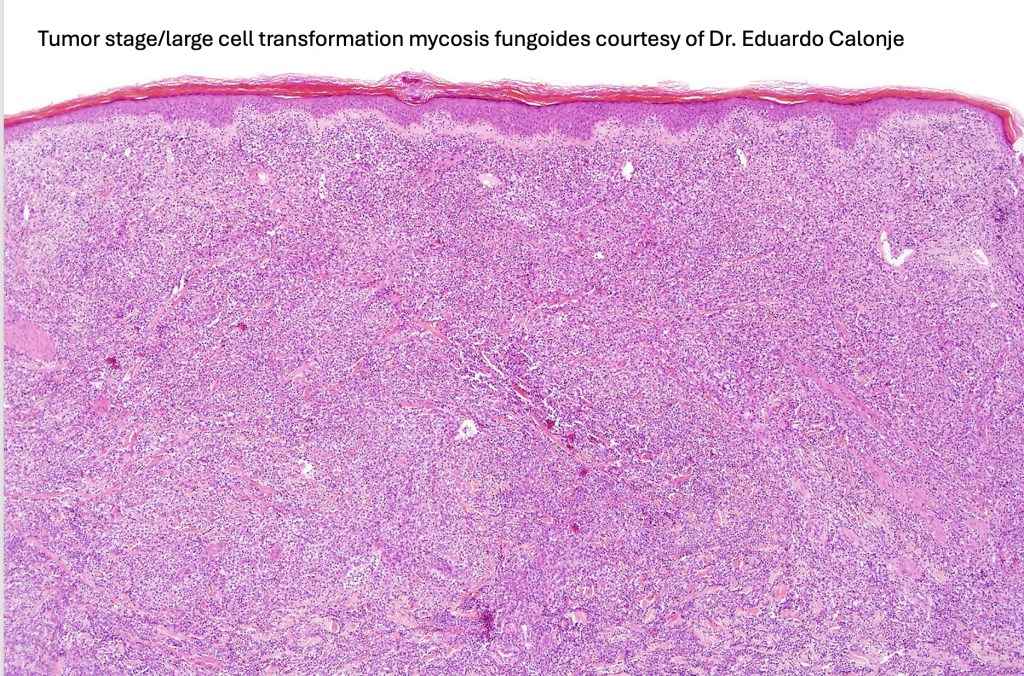

Histological features

The histological hallmark of mycosis fungoides is the presence of large atypical lymphocytes with a convoluted/cerebriform nuclear border (Sézary cells). These may be found at the epidermal-dermal jnuction and as collections within the epidermis (Pautrier microabscess). These are most easily found in plaque stage disease. The epidermal component can be subtle in patch stage disease and is often lost in tumor stage dsease. The classification into patch, plaque & tumor stage disease is less helpful histologically as the features merge from one to the other. It is all a matter of degree.

Tumor Stage Disease

•Epidermotropism is often minimal or absent

•Dense, broad diffuse or nodular, dermal infiltrate often extending into the subcutaneous fat

•Abundant Sézary cells. Frequently accompanied by very pleomorphic forms

•Mitoses often abundant, frequently abnormal

•CD30 expression correlates with transformation (cells X4 size of small lymphocytes comprising 25% or more of the infiltrate or the presence of a distinct large nodule)